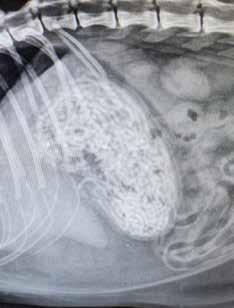

“It is cute to see a cat playing with a hair tie, but it is not worth the risk,” said Dr. Tracy. Take the case of Juliet, who was brought to Charleston Animal Society along with two other cats by a Good Samaritan who said they had been left outside a home when their family moved out of state. Juliet seemed fine at first, but eventually she began not eating and then became

lethargic. Radiographs showed she had an unusual sort of blockage in her stomach that would kill her if it was not removed.

What Charleston Animal Society Associate Director of Veterinary Care Dr. Leigh Jamison found was simply unbelievable — a seemingly endless bundle of strings that continued to come out as Dr. Jamison surgically removed them. “I’ve never seen anything like it,” Dr. Jamison said.

After everything was pulled out, the surgery team counted more than three dozen hair ties blocking Juliet’s stomach, which had prevented her from eating or processing food. Tragically, the blockage caused a fatal buildup of fat in her liver. The emergency surgery and electrolyte treatment were not enough, and Juliet died.

BELOW: These 28 hair ties were pulled from the stomach of Juliet. BELOW LEFT: An x-ray shows a mass of string in Juliet’s stomach, that turned out to be a deadly bundle of hair ties.